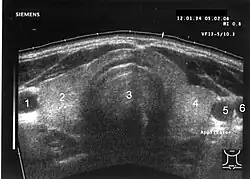

Adenom štítné žlázy je benigní (nezhoubný) nádor štítné žlázy. Může se vyskytovat solitárně i mnohočetně. Mnohočetný výskyt je typický pro tzv. polynodózní strumu, což je mnohočetné postižení štítné žlázy adenomy a cystami.

U jakékoliv hmatné rezistence v oblasti štítné žlázy je vždy třeba vyloučit maligní (zhoubný) nádor. V diagnostice adenomu (a odlišení maligního nádoru) se uplatňuje: anamnéza, fyzikální vyšetření (aspekce, palpace), ultrasonografie (USG) a tenkojehlová aspirační biopsie (FNAB) s následným cytologickým vyšetřením.